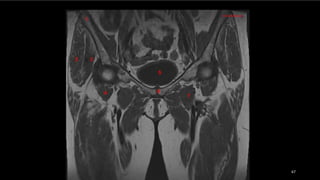

• El músculo glúteo mayor (GMa).

• músculos semimembranoso (sm), semitendinoso (st)

y la cabeza larga del bíceps femoral (elb).

• músculo semimembranoso tiene su propio tendón

(1).

• semitendinoso y la cabeza larga del bíceps se originan

en la cara lateral de la tuberosidad isquiática -en un

tendón común (2).

• nervio ciático (NC). TM, trocánter mayor.

• El músculoglúteo mayor (GMa). • músculos semimembranoso (sm), semitendinoso (st) y la cabeza larga del bíceps femoral (elb). • músculo semimembranoso tiene su propio tendón (1). • semitendinoso y la cabeza larga del bíceps se originan en la cara lateral de la tuberosidad isquiática -en un tendón común (2). • nervio ciático (NC). TM, trocánter mayor.

• #64  Características anatómicas de los músculos y tendones de la región posterior (isquiocrurales) de la cadera. Dibujo de una vista posterior de la cadera que ilustra la inserción de los músculos posteriores en la tuberosidad isquiática (T~. El músculo glúteo mayor (GMa) se muestra semitransparente sobre los músculos isquiocrurales. Debajo de éste, obsérvense los músculos semimembranoso (sm), semitendinoso (st) y la cabeza larga del bíceps femoral (elb) . El músculo semimembranoso tiene su propio tendón (1); sin embargo, el semiitendinoso y la cabeza larga del bíceps se originan en la cara lateral de la tuberosidad isquiática (T~ en un tendón común (2). Obsérvense las relaciones entre estos músculos y el nervio ciático (NC). TM, trocánter mayor.